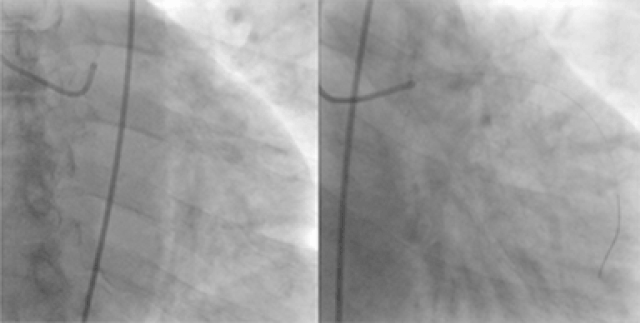

Dr. Tariq Rasool is a highly skilled Interventional Cardiologist with extensive experience in diagnosing and treating complex heart conditions. He specializes in coronary interventions, heart failure management, arrhythmia treatment, and emergency cardiac care. With a patient-centered and evidence-based approach, Dr. Rasool ensures accurate diagnosis, timely treatment, and compassionate care for every patient.